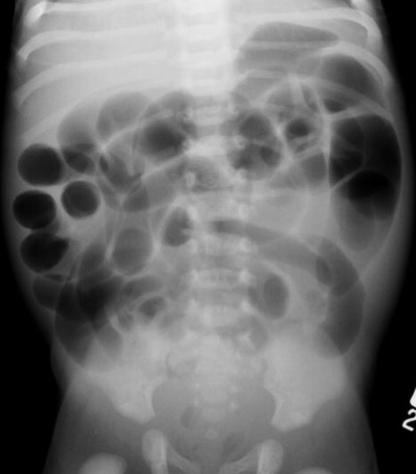

Aspect radiologique ASP d'une

megacolon congenitale : Image dilate aerique du

colon en amont de la portion inerve (

aganglionaire ) . |

Image distendue aerique du

colon descendent et colon transverse d'une megacolon

congenitale .Cliche radiologique ASP de face . |

Image radiologique ASP

une toxic megacolon : Colon transverse dilate

aerique avec epaissisement de la paroie et des

haustrations en forment de doitier imprime "

thumbprinting sign " |

Image

radiologique ASP en decubitus dorsale : Toxic

megacolon par colite ulceree , la colon transverse

et une partie de colon descecdent est dilate et sa

paroie est perdre des haustral |